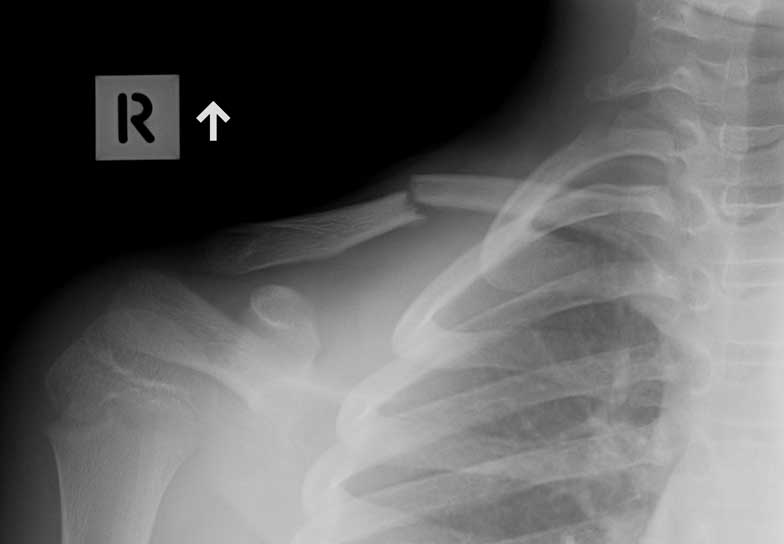

This young man first fractured his clavicle when he was 9 years old and it was treated conservatively and healed. Then three years later he fell from his skateboard and broke it again and was again treated conservatively but this time did not heal and continued to be painful so he had a plate put on and he had healed eight weeks later.

Malunion fracture before surgery

Malunion fracture after surgery

Move the slider to compare before surgery and 8 weeks after surgery